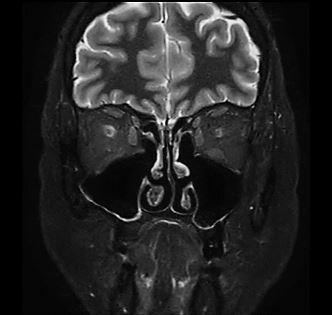

Beispielaufnahmen von einer MRT der Nasennebenhöhlen (NNH)

Die MRT der Nasennebenhöhlen zeigt ihren Mehrwert vor allem in der Diagnostik von akuten oder chronischen Entzündungen sowie in der Früherkennung und Unterscheidung von gut- und bösartigen Tumoren. Auch bei angeborenen Fehlbildungen, bei Verdacht auf Fremdkörper oder zur Operationsvorbereitung liefert sie wertvolle Informationen.

Gerade wenn Beschwerden über einen längeren Zeitraum bestehen und die Ursache unklar ist, ist die NNH-MRT sinnvoll. Die besonders gute Auflösung der Bilder macht die MRT zu einem zuverlässigen Begleiter in der modernen HNO-Diagnostik. Mit den gewonnenen Erkenntnissen können gezielte Behandlungsmaßnahmen eingeleitet oder unnötige Eingriffe vermieden werden.

- Nasennebenhöhlen: Kieferhöhlen, Stirnhöhlen, Siebbeinzellen, Keilbeinhöhlen

- Nasengänge und Nasenmuscheln

- Schleimhäute und deren Zustand

- Nasenscheidewand (z. B. bei Verkrümmungen)

- Weichteilgewebe, Nervenverläufe (z. B. Trigeminusnerv) und Blutgefäße

- Schädelbasis und angrenzende Hirnstrukturen